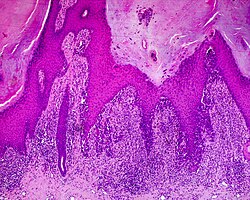

Histology[edit | edit source]

The main characteristic of acral lentiginous melanoma is continuous proliferation of atypical melanocytes at the dermoepidermal junction.[16] Other histological signs of acral lentiginous melanoma include dermal invasion and desmoplasia.[17]

According to Scolyer et al.,[18] ALM "is usually characterized in its earliest recognisable form as single atypical melanocytes scattered along the junctional epidermal layer".